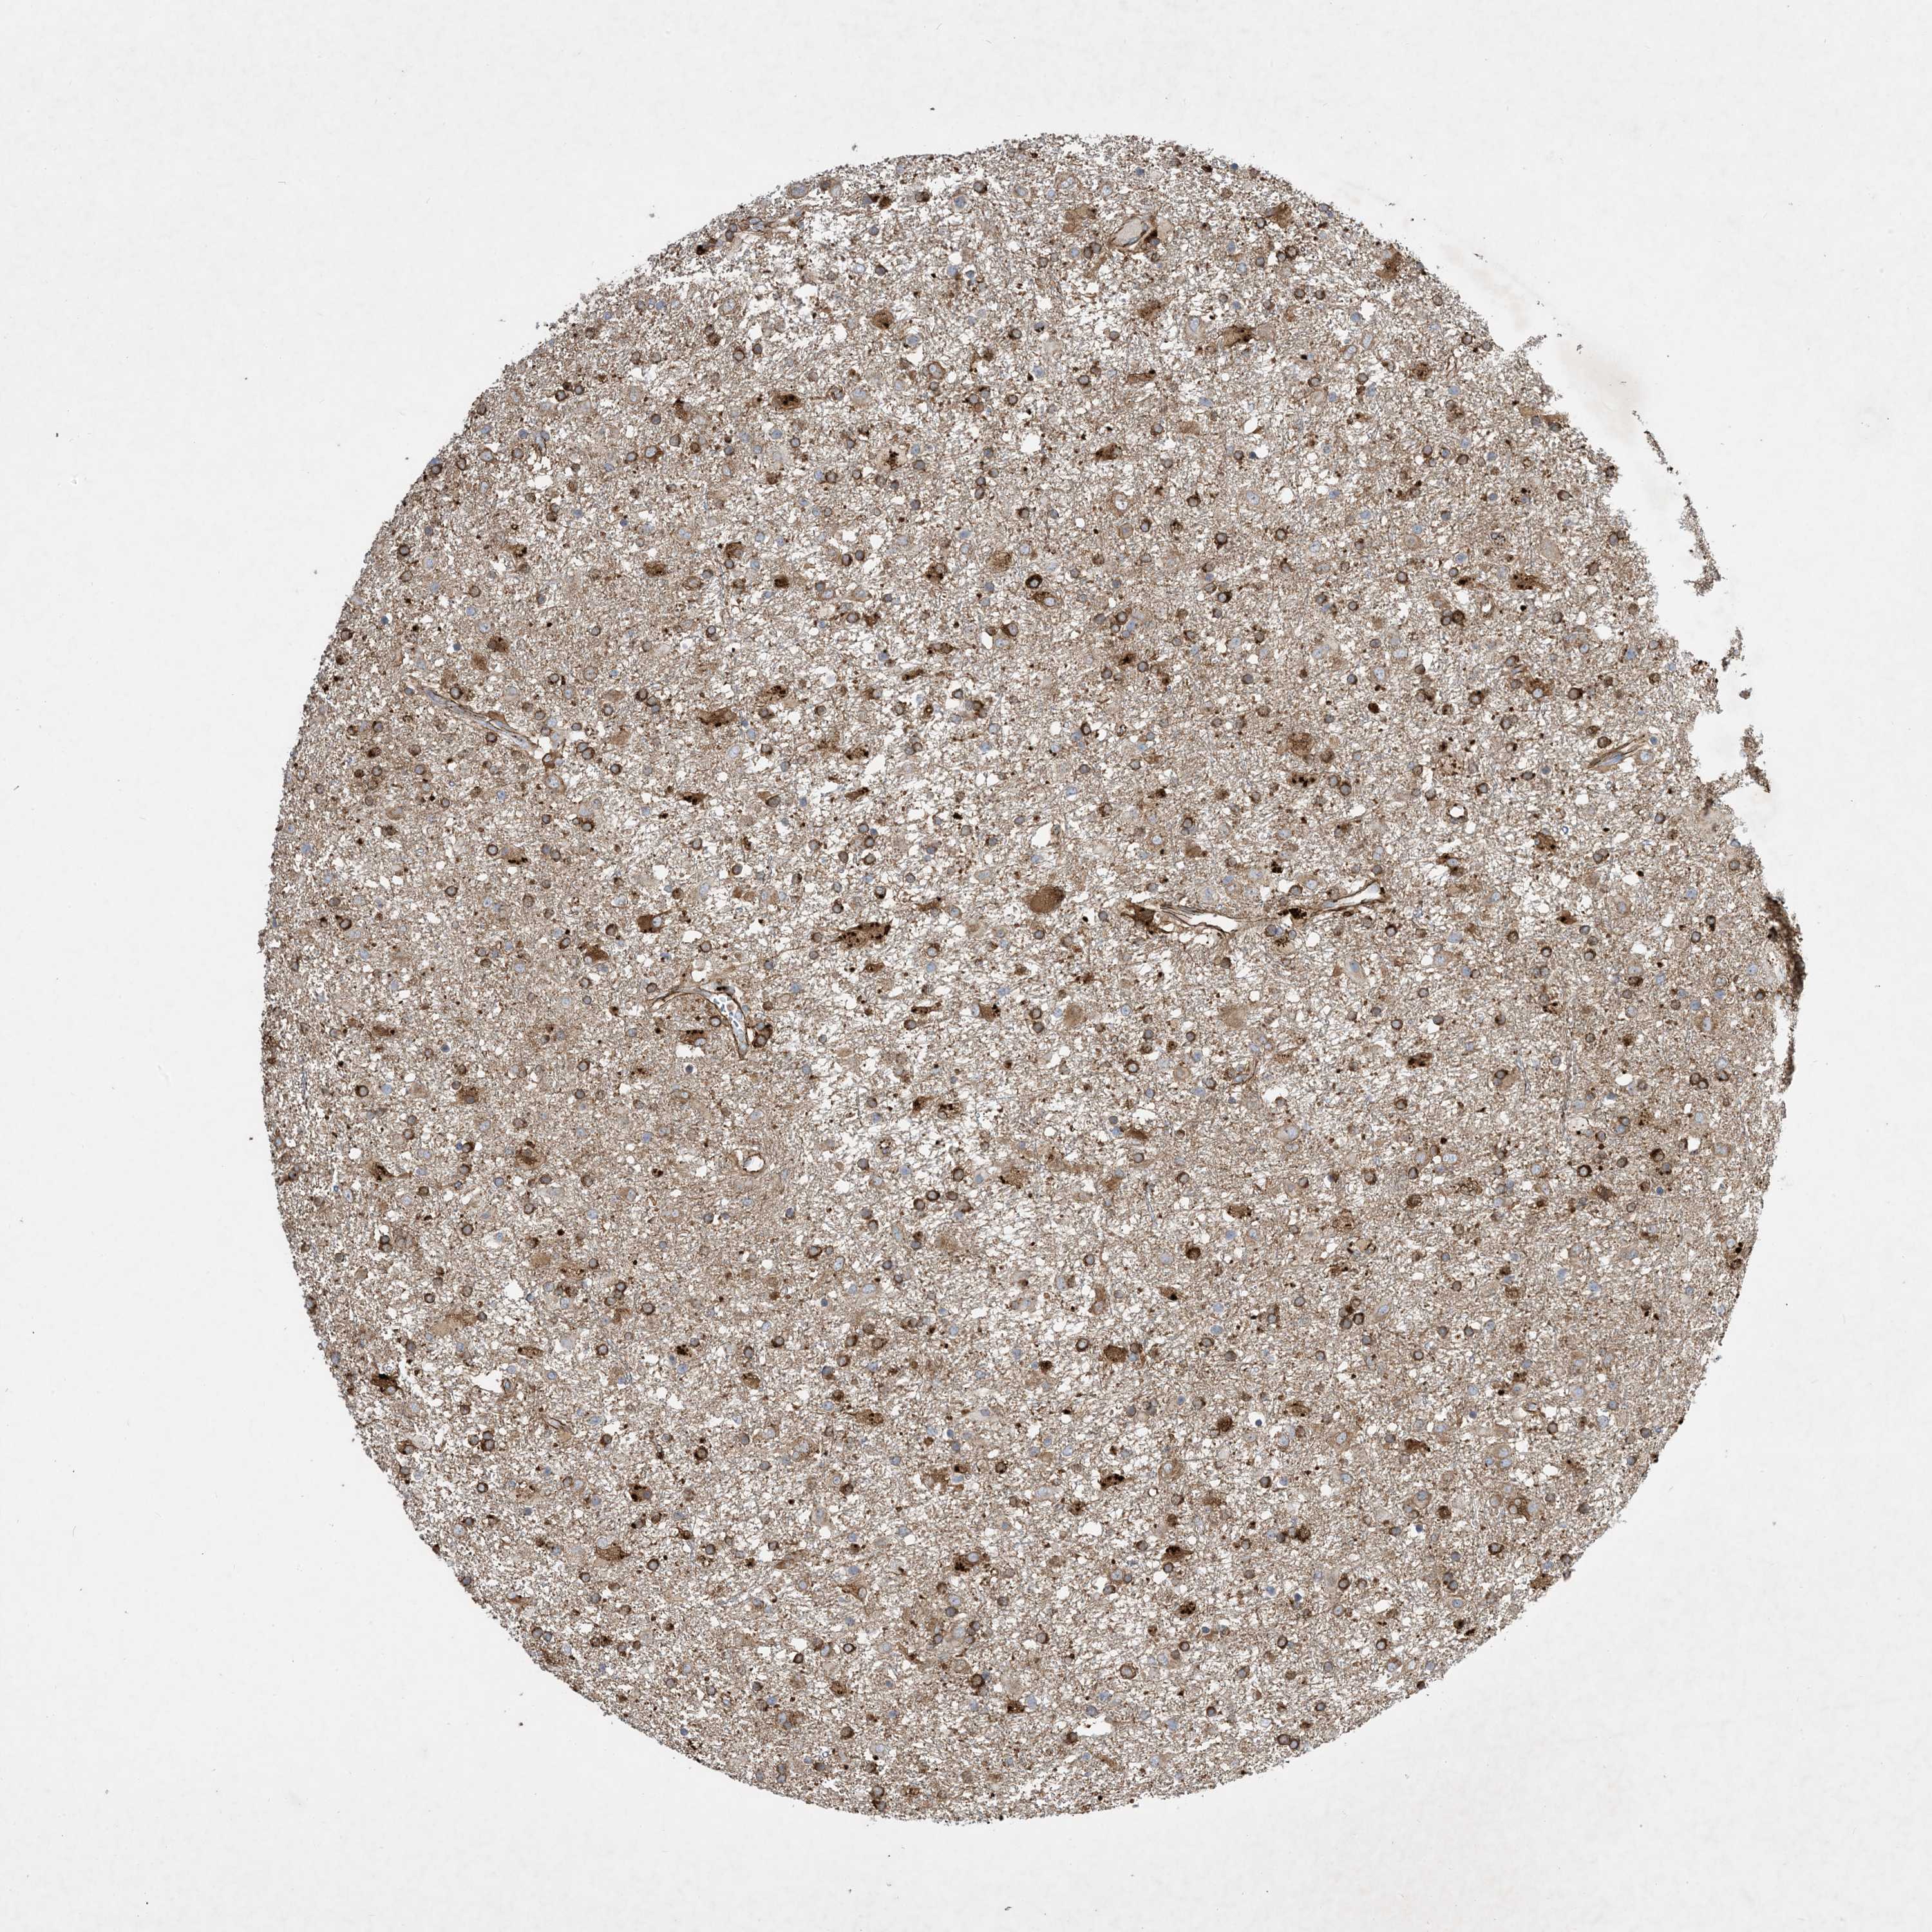

GLIOMA - Protein expressioni

A mouse-over function shows sample information and annotation data. Click on an image to view it in a full screen mode. Samples can be filtered based on level of antibody staining by selecting one or several of the following categories: high, medium, low and not detected. The assay and annotation is described here.

Note that samples used for immunohistochemistry by the Human Protein Atlas do not correspond to samples in the TCGA dataset.

Antibody stainingi

Antibody staining in the annotated cell types in the current human tissue is reported as not detected, low, medium, or high, based on conventional immunohistochemistry profiling in selected tissues. This score is based on the combination of the staining intensity and fraction of stained cells.

Each image is clickable and will lead to virtual microscopy that enables deeper exploration of all samples and also displays staining intensity scores, fraction scores and subcellular localization as well as patient and tissue information for each sample.

Antibody HPA035599

Staining

High

Medium

Low

Not detected

Intensity

Strong

Moderate

Weak

Negative

Quantity

>75%

75%-25%

<25%

None

Location

Nuclear

Cytoplasmic/membranous

Cytoplasmic/membranous,nuclear

Glioma, malignant, High grade

Glioma, malignant, Low grade

Glioblastoma, NOS